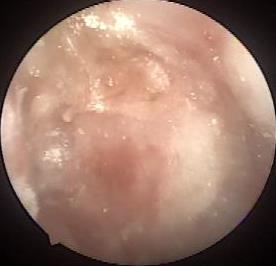

• 京都胃炎评分、胃蛋白酶原联合胃泌素-17预测中老年幽门螺杆菌感染阳性的萎缩性胃炎患者的最佳截断值

摘要:目的 以胃镜病理活检作为金标准,探讨基于胃镜检查的京都胃炎评分、胃蛋白酶原(PG)联合胃泌素-17(G-17)预测中老年幽门螺杆菌(Hp)感染阳性的萎缩性胃炎患者的最佳截断值。方法 选择2022年8月-2023年6月于该院消化内科就诊并经胃镜检查和病理活检确诊为萎缩性胃炎的120例中老年患者作为研究对象,且所有患者均经14C-尿素呼气试验确诊为Hp阳性。入组后对每位患者进行胃镜病理活检,并根据活检结果分为萎缩性胃炎组(AG组)68例和非萎缩性胃炎组(非AG组)52例;根据木村-竹本(Kimura-Takemoto)分类法,进一步对68例萎缩性胃炎进行分组,分为轻度AG组(n = 12)、中度AG组(n = 32)和重度AG组(n = 24)。基于胃镜检查,对所有患者进行京都胃炎评分,同时,用化学发光法测定患者的血清胃蛋白酶原Ⅰ(PGⅠ)、胃蛋白酶原Ⅱ(PGⅡ)及G-17水平,并计算胃蛋白酶原比值(PGR)。使用受试者操作特征曲线(ROC curve)评价京都胃炎评分、血清PG和G-17对中老年Hp感染阳性的萎缩性胃炎患者的预测价值。结果 AG组与非AG组京都胃炎评分、血清PGⅠ、PGR和G-17水平比较,差异均有统计学意义(t = 13.38,P = 0.000;t = 50.84,P = 0.000;t = 26.44,P = 0.000;t = 9.44,P = 0.000),AG组京都胃炎评分高于非AG组(P < 0.05),AG组血清PGⅠ、PGR和G-17水平均低于非AG组(P < 0.05);AG组与非AG组血清PGⅡ水平比较,差异无统计学意义(t = 1.24,P = 0.219)。轻度AG组、中度AG组和重度AG组京都胃炎评分、血清PGⅠ、PGR和G-17水平比较,差异均有统计学意义(F = 33.95,P = 0.000;F = 81.99,P = 0.000;F = 67.36,P = 0.001;F = 33.50,P = 0.004),轻度AG组京都胃炎评分低于中度AG组和重度AG组(P < 0.05),中度AG组低于重度AG组(P < 0.05)。轻度AG组和中度AG组血清PGⅠ及PGR水平高于重度AG组(P < 0.05),轻度AG组高于中度AG组(P < 0.05)。轻度AG组血清G-17水平低于中度AG组和重度AG组(P < 0.05),中度AG组和重度AG组比较,差异无统计学意义(P > 0.05)。轻度AG组、中度AG组和重度AG组血清PGⅡ水平比较,差异无统计学意义(F = 1.03,P = 0.364)。京都胃炎评分、血清PGⅠ、PGR和G-17预测中老年Hp感染阳性的萎缩性胃炎患者的最佳截断值分别为2.78分、38.26 μg/L、1.92和9.54 pmol/L。其中,京都胃炎评分预测中老年Hp感染阳性的萎缩性胃炎患者的曲线下面积(AUC)为0.780,敏感度为71.42%,特异度为78.62%;PGⅠ预测中老年Hp感染阳性的萎缩性胃炎患者的AUC为0.757,敏感度为66.27%,特异度为83.25%;PGR预测中老年Hp感染阳性的萎缩性胃炎患者的AUC为0.792,敏感度为76.23%,特异度为87.35%;G-17预测中老年Hp感染阳性的萎缩性胃炎患者的AUC为0.672,敏感度为60.24%,特异度为74.28%;四者联合预测中老年Hp感染阳性的萎缩性胃炎患者的AUC为0.871,敏感度为81.28%,特异度为87.36%。结论 基于胃镜检查的京都胃炎评分联合血清PGⅠ、PGR和G-17检测,对于中老年Hp感染阳性的萎缩性胃炎患者,具有良好的预测价值,其预测中老年Hp感染阳性的萎缩性胃炎患者的最佳截断值分别为2.78分、38.26 μg/L、1.92和9.54 pmol/L。